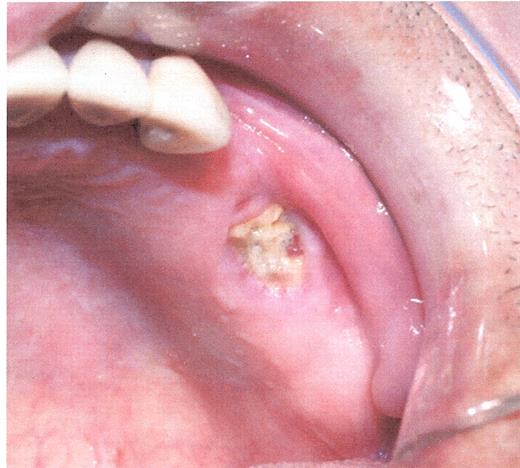

Stage I osteonecrosis of the jaw (ONJ). Patient with myeloma on zoledronic acid for 18 months.

Stage II osteonecrosis of the jaw (ONJ). Patient on zoledronic acid for 18 months.